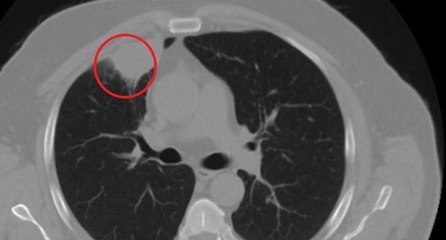

Dünya tıp literatüründe bir ilk: Covid-19, akciğer kanserini taklit etti